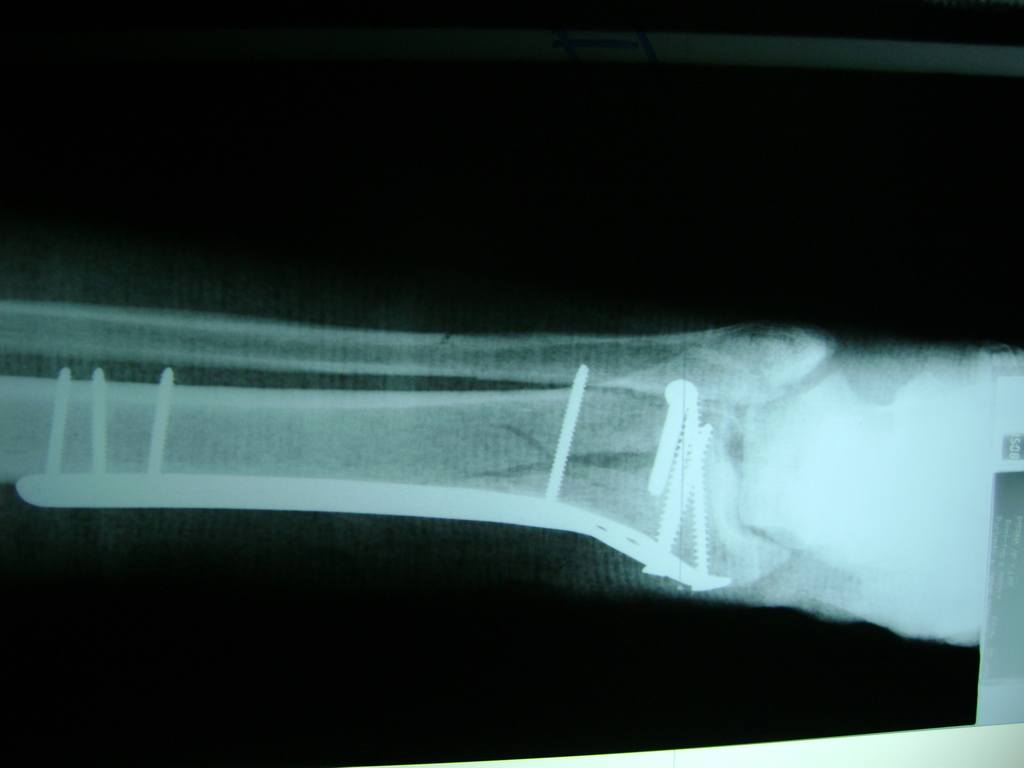

Cirugias en El Salvador - Perone y Tibia

Aunque cada uno de estos huesos puede fracturarse por separado, normalmente la rotura es una lesión que se produce de forma conjunta

La mayor parte de las roturas implican a la parte proximal del hueso (parte del hueso próximo a la rodilla) o a la parte distal (parte del hueso cerca del tobillo).

Debido a la fina cobertura de piel que recubre la tibia y el peroné, las fracturas generalmente son abiertas, es decir, el hueso roto rasga la piel, atravesándola. Las fracturas de tibia y peroné generalmente se producen por un fuerte impacto o torsión.